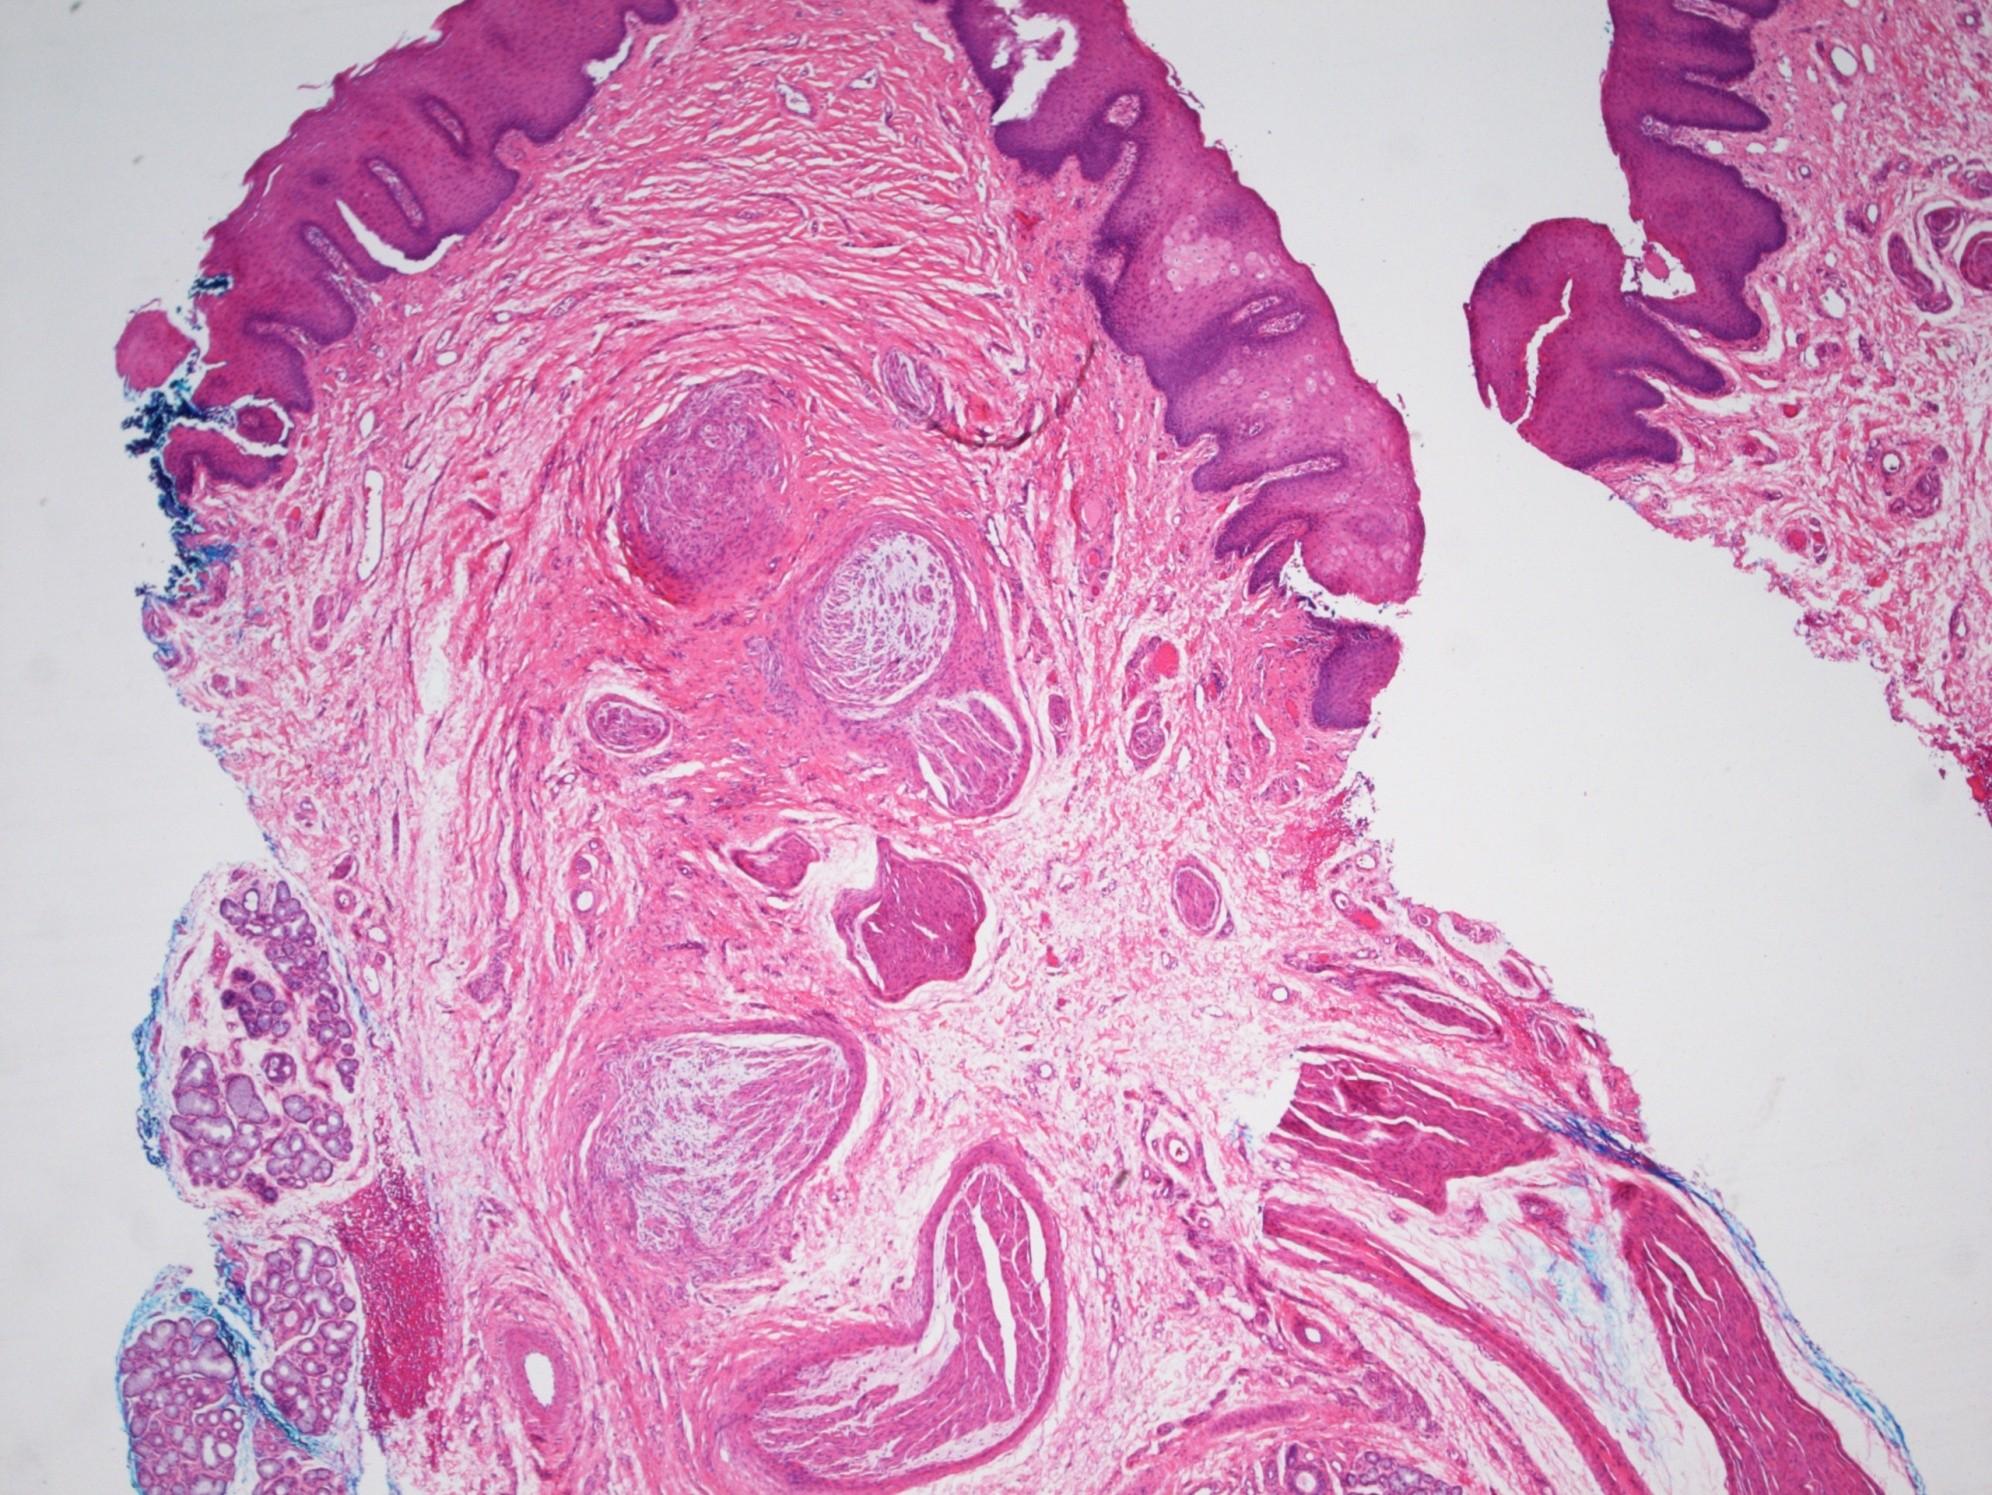

Odontogenic keratocyst

 Officially now a tumour (WHO 2005)

 In syndrome: multiple and earlier onset than sporadic and greater tendency to recur

 Is the only odontogenic cyst to keratinize

 Basal cell palisading and corrugated surface typical

 Satellite and daughter cysts more prevalent in syndromic patients